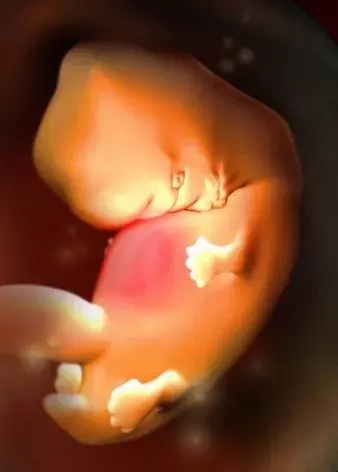

6周:

胎兒長到0.85厘米,胎兒頭部、腦泡、額面器官、呼吸、消化、神經等器官分化,B超胎囊清晰可見,并見胎芽及胎心跳。

7周:

胎兒長到1.33厘米,胚胎已具有人雛形,體節已全部分化,四肢分出,各系統進一步發育。B超清楚看到胎芽及胎心跳,胎囊約占宮腔的l/3。此時還聽不到胎心音,但胚胎的心臟已經劃分成左心房和右心室,每分鐘大約跳150下。